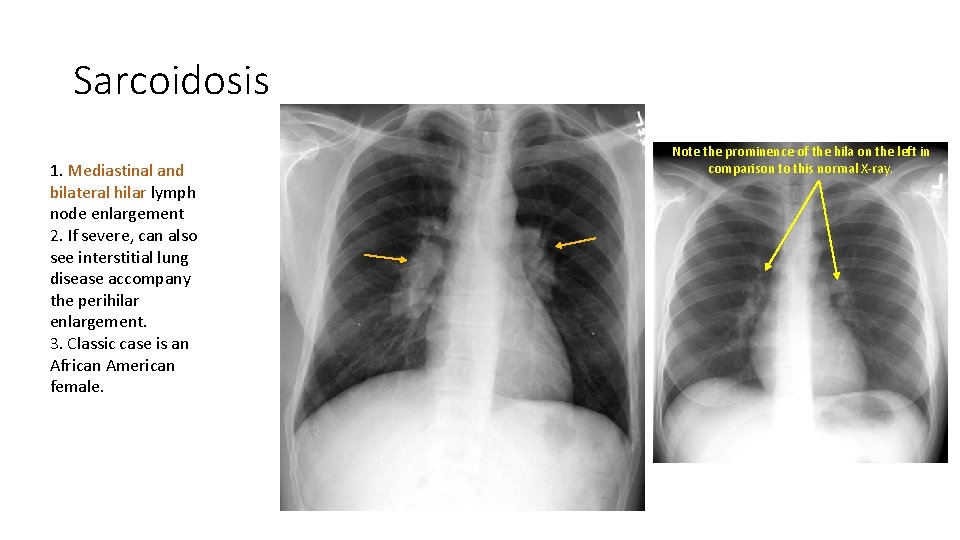

Sarcoidosis 1. Mediastinal and bilateral hilar lymph node enlargement 2. If severe, can also see interstitial lung disease accompany the perihilar enlargement. 3. Classic case is an African American female. Note the prominence of the hila on the left in comparison to this normal X-ray.